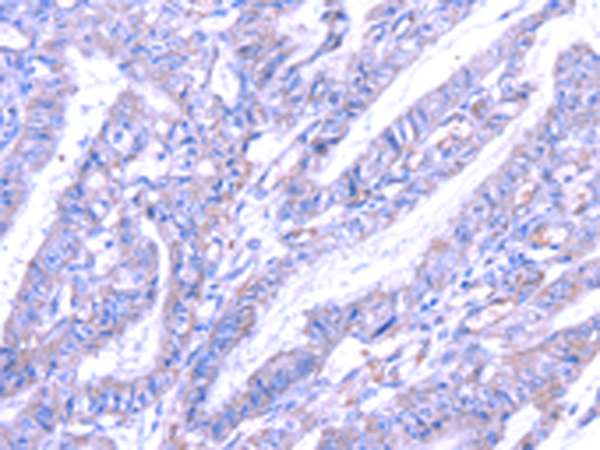

分类: 科研抗体货号: P08819别名: ST1B1; ST1B2; SULT1B2应用: WB,IHC反应种属: Human